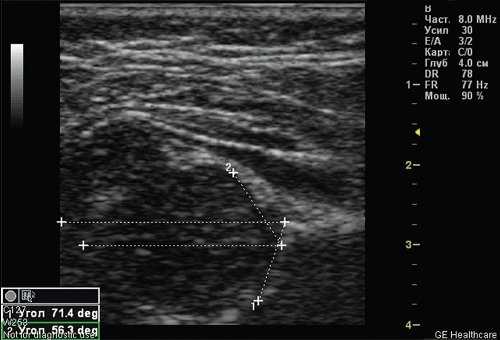

Тип 2а тазобедренных суставов (рис. 3) диагностирован у 46 (11,6%) детей. Это вариант физиологической задержки развития тазобедренных суставов у детей в возрасте до 12 нед, при котором угол α меньше 59°, но больше 50°, соответственно угол β больше 60°.

Рис. 3. Тазобедренный сустав тип 2а.

1 - угол α=55,9°;

2 - угол β=69,2°.